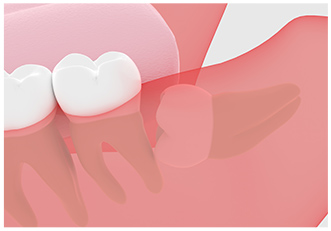

隣の歯を圧迫している状態です。むし歯などのお口のトラブルが起こりやすく、かみ合わせや歯並びに影響が出る場合もあるので、抜歯をおすすめします。

完全に歯ぐきの中で横向きにはえている状態です。

抜歯するためには、歯ぐきを切開してめくりあげ、歯の頭の部分と骨の一部分を削り取り、分割しながら抜歯していきます。